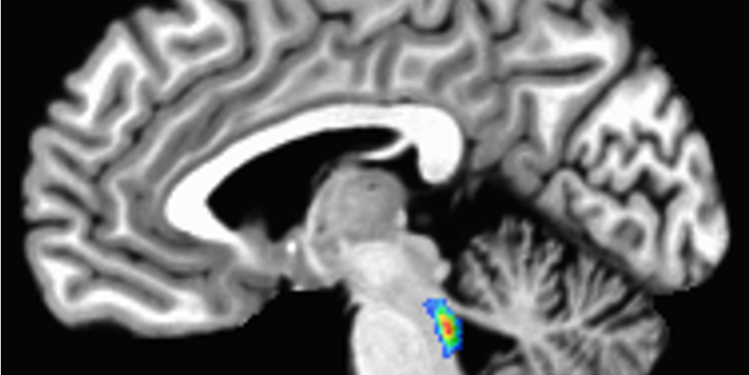

A scan of the brain with the locus coeruleus lit up in the brain stem

The locus coeruleus, which means ‘blue spot,’ is located in the brain stem, the lowest part of the brain.

Elizabeth Riley, CC BY-SA

The locus coeruleus sits in the brain stem, the lowest part of the brain. Its name, “blue spot,” comes from a pigment called neuromelanin that its cells produce.